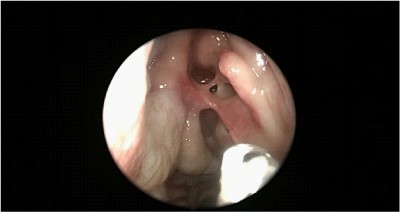

8. The first time was FESS. We proceeded to interruption of the synechiae at level of nasal-frontal duct to reach the region of the mucus-piocele that overlooked the left orbit (Figure 4).

Figure 4 Left synechia at level of nasal-frontal duct.